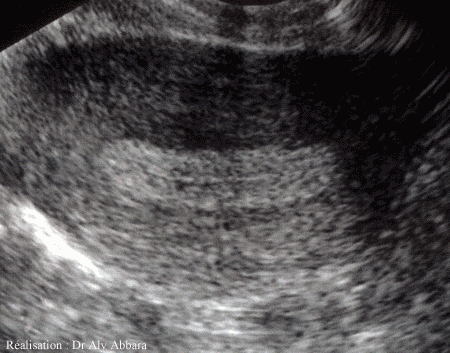

- À l'échographie :

- Pas de grossesse intra-utérine identifiable (sauf s'il s'agit exceptionnellement d'une grossesse hétérotopique, c'est-à-dire présence de deux grossesse, intra-utérine et extra-utérine, d'où l'intérêt d'explorer l'ensemble de petit pelvis même après avoir constaté la présence d'une grossesse implantée dans la cavité utérine).

- L'endomètre est habituellement peu épais dans les grossesses extra-utérines ,

,

; le plus souvent, il ne mesure que quelques millimètres, mais un endomètre épaissi

(15 à 25 mm, comme c'est le cas dans les grossesses intra-utérines débutantes

), voire très épaissi

, n'exclut pas le diagnostic de grossesse extra-utérine.